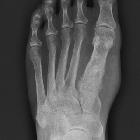

Unlike conventional chondrosarcomas, they arise from the surface of the bone, lifting the periosteum over themselves as a fibrous pseudocapsule. The underlying cortex is usually thickened or may be eroded, however, extension into the medullary cavity is not usual. Where the periosteum is lifted a Codman triangle may be seen. In addition to the usual chondroid matrix, metaplastic ossification is also common.

They typically arise from long bones, with a predilection for the posterior aspect of the distal femur.